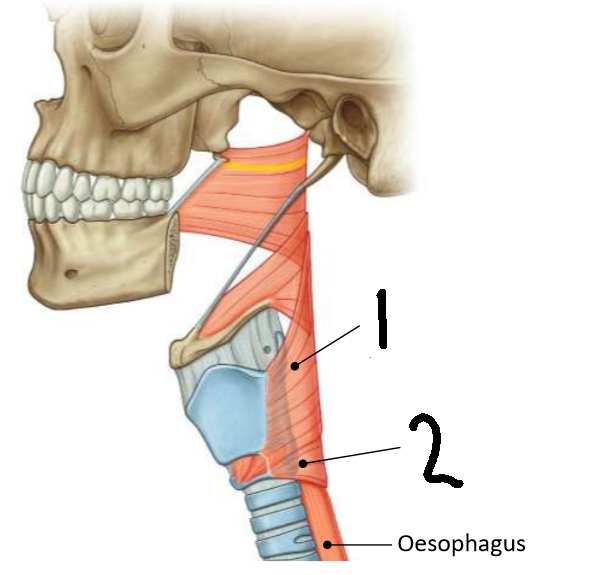

What muscle is this?

inferior constrictor

Which part of the muscle is 1?

thyropharyngeus

Which part of the muscle is 2?

cricopharyngeus

What are the attachments of this muscle?

oblique line of thyroid cartilage, cricothyroid tendon, cricoid cartilage → pharyngeal raphe